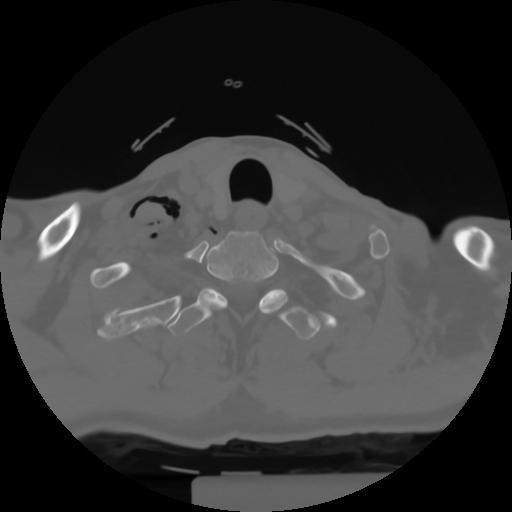

10 P.BLANDAS,,Axial,2.0,P.BLANDAS,,